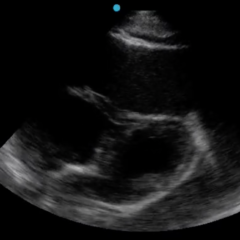

In this case, we discuss a 51-year-old female with history of anxiety, depression, and alcohol abuse who presented for altered mental status, focal neurological deficits, and seizure. She was found to be significantly hypertensive. Non-contrast computed tomography (CT) scan imaging of the head revealed changes suggestive of posterior reversible encephalopathy syndrome (PRES), which was ultimately confirmed by MRI imaging. The patient was treated appropriately with anti-hypertensive therapy and seizure prophylaxis. Due to the prompt recognition of PRES and immediate management, the patient was able to make a favorable neurological recovery. This case highlights the importance of including (PRES) as part of a wide differential diagnosis for a patient with altered mental status, significantly elevated blood pressure, and focal neurological deficits. Early recognition and treatment of PRES can improve neurological outcomes and quality of life for patients.